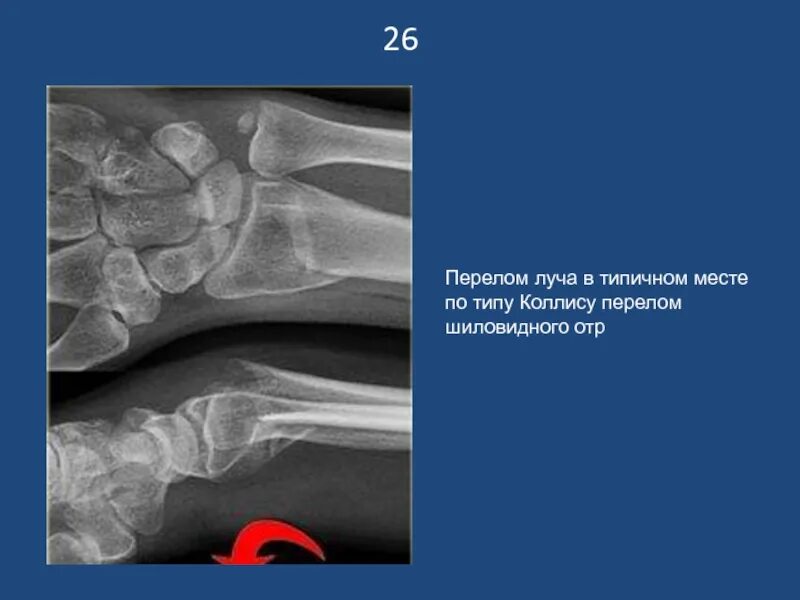

Перелом луча в типичном месте код мкб